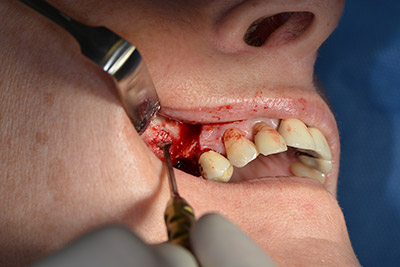

The fenestration was prepared at 35,000 rpm and then the nasal mucosa were prepared in the cranial direction (Fig. 13 to 14).

The implant was then placed and the bone built up. In this case, because of the size of the augmentation region, autologous bone chips, harvested with an osseous trap as drilling chips from implantation 16 and fenestration 14, were mixed with bone replacement material.

An absorbable membrane was used as the barrier in the buccal direction and covered the augmentation. Finally, saliva-proof sutures were placed (Fig. 15 to 19).